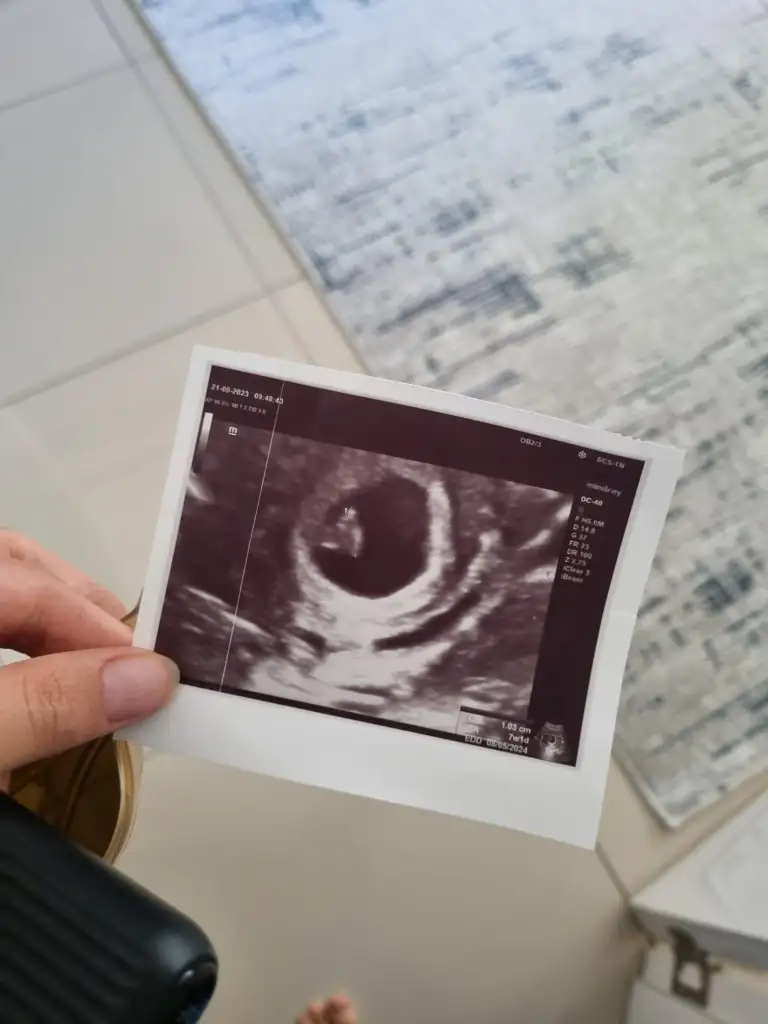

Selam bizede bakarmısınız ilki 6haftalık vajinal diğeri 7+3 karından bakıldı

• IMG_8431.webp

IMG_8431.webp

31 KB · Görüntüleme: 87

• 45a639a2-0c77-4877-8f07-fa6d62c7beef.webp

45a639a2-0c77-4877-8f07-fa6d62c7beef.webp

29,6 KB · Görüntüleme: 82

yorumunuz için teşekkürler solda olunca erkek sağda olunca kız diyorlardı hayırlısı bekleyip göreceğiz